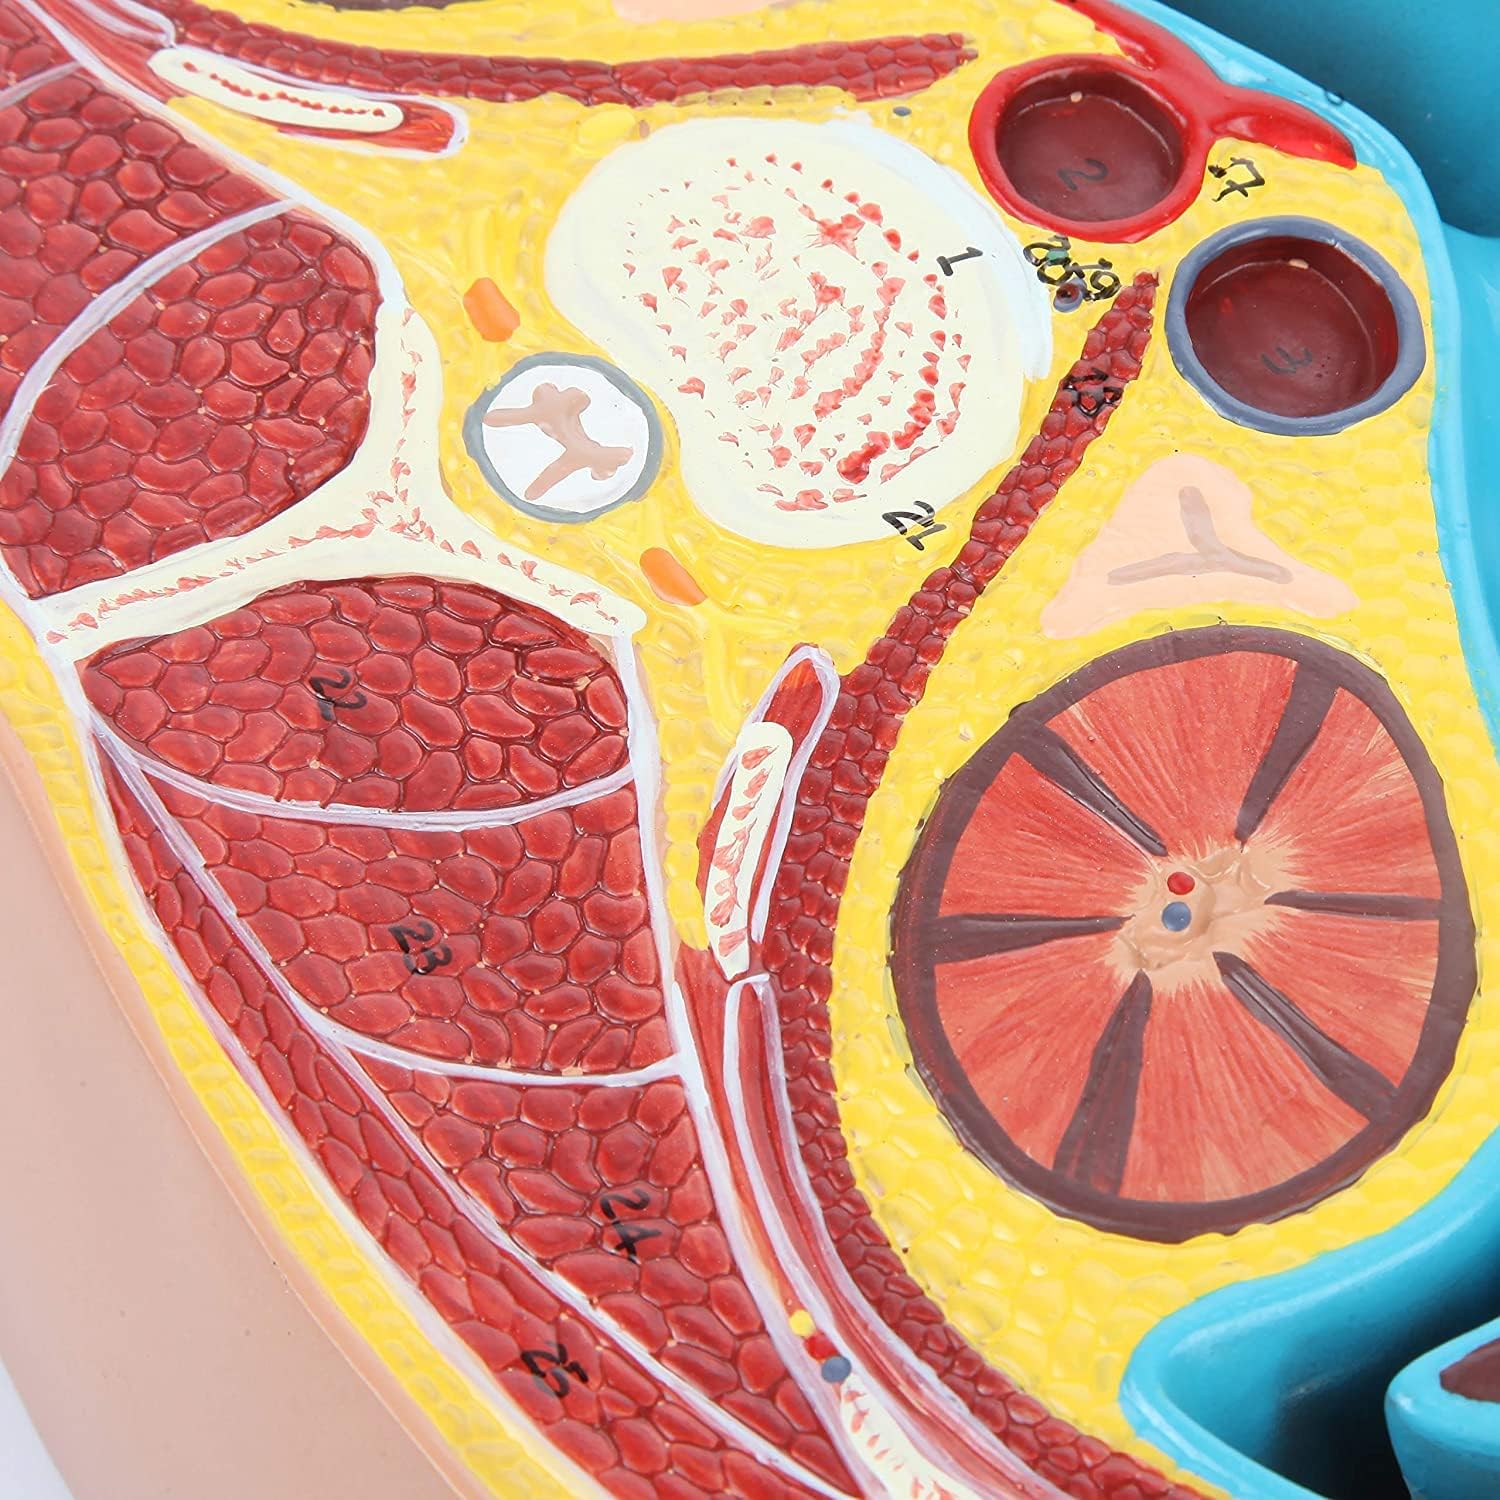

Hand Painted: made of food-grade PVC materials, computer color matching, high-grade hand-painted.

Anatomical Standard:According to the normal anatomical posture, the flat mediastinum is used as a cross-cut design, and the height of the eighth thoracic vertebra is shown in detail.